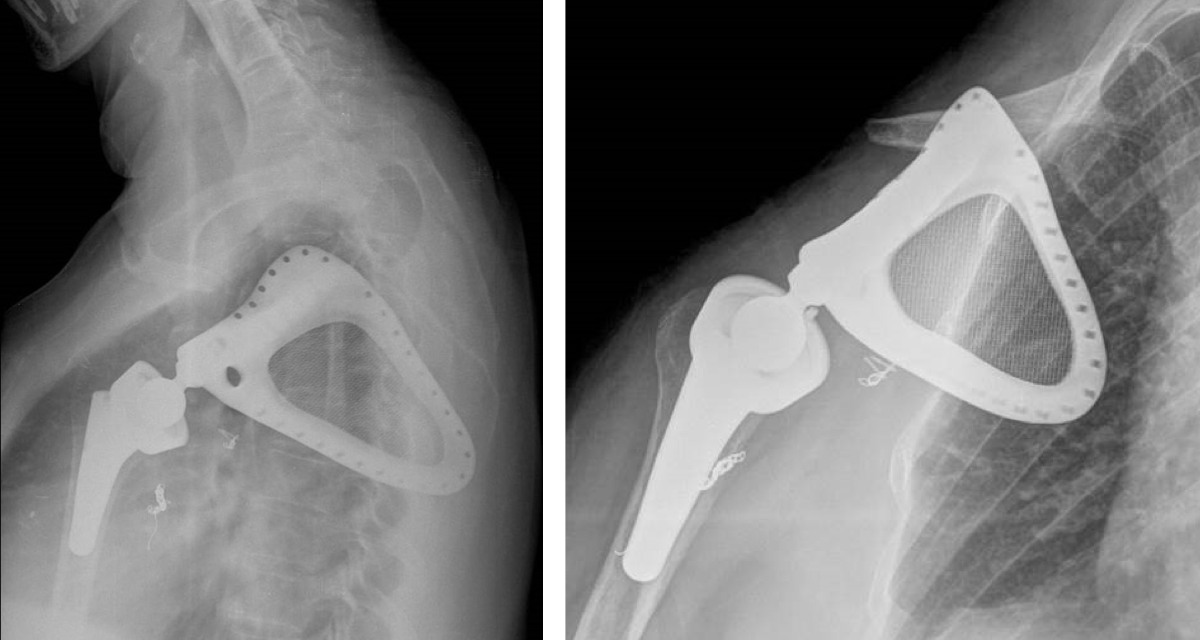

Post-op x-rays

- Total scapula replacement, right side, made of Ti6Al4V, with TrabecuLink structure

- Glenoideal head, 22 mm diameter, made of Ti6Al4V with hypoallergic PorEx coating (TiNbN)

- Extended Reverse Tray

- Constrained PE-Insert with locking ring

- Scapular replacement with special TrabecuLink filling for promotion of connective tissue attachment

- Humeral fixation with cemented Embrace stem